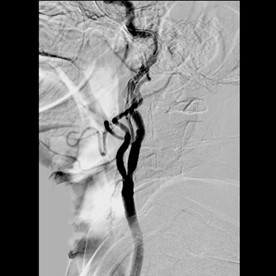

La angiotomografía reveló una obstrucción completa de la arteria carótida interna derecha y una obstrucción de 70% de la contralateral, en la angiografía cerebral se confirmó la obstrucción de la carótida interna izquierda de 85% con una buena colateralidad dada por el sistema vértebro-basilar (figura 1). Estos hallazgos sugirieron ataques isquémicos transitorios manifestados como síndrome de limb-shaking.

Figura 1. Angiografía cerebral: obstrucción del 85 % de arteria carótida interna izquierda.